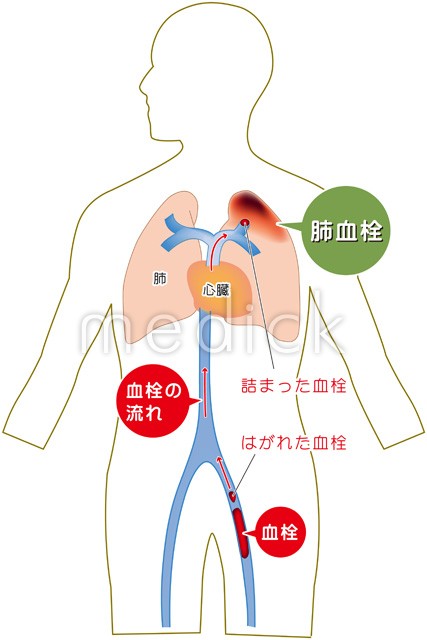

血栓性静脈炎とはの説明スライド - 医療のイラスト・写真・動画、素材販売サイトのメディック medick。

肺血栓症のイラスト - 医療のイラスト・写真・動画、素材販売サイトのメディック medick。

肺血栓塞栓症・エコノミークラス症候群 男性 のイラスト – フリーイラスト素材集 KuKuKeKe。

肺血栓塞栓症のベクター画像イラスト。血管血栓症」のベクター画像素材 ロイヤリティフリー737751463Shutterstock。

エコノミークラス症候群 深部静脈血栓症 メカニズムのイラスト素材29374549- PIXTA。